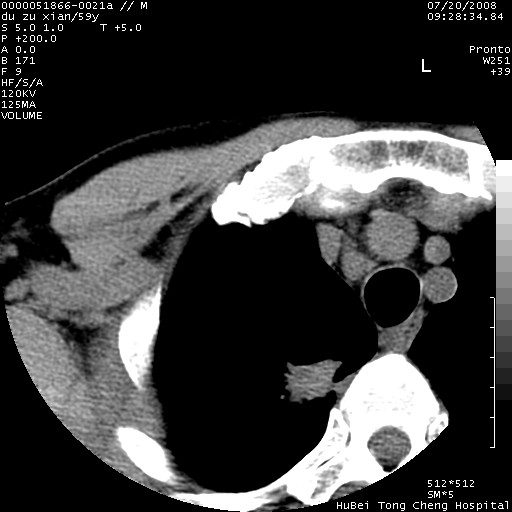

以下是引用宇宙ct在2008-8-25 23:21:00的发言:[br]右肺周围性肺癌并肋骨转移,纵隔淋巴结转移。

以下是引用zsl6918在2008-8-25 22:40:00的发言:[br]右肺周围性肺癌并肋骨转移,纵隔淋巴结转移。

以下是引用zy_zj在2008-8-26 15:24:00的发言:[br]单从病变本身,我倾向良性炎性病变,但肋骨转移了,所以说是考虑右肺周围性肺癌并肋骨、纵隔淋巴结转移可能性大。